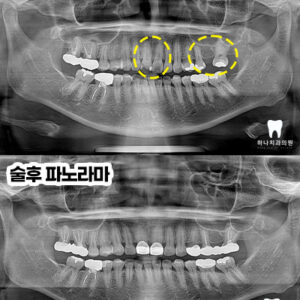

울산삼산동치과 크라운 퍼포레이션과 보철 교체 시기

울산삼산동치과 크라운 퍼포레이션과 보철 교체 시기   안녕하세요! 하나치과입니다~:) ​ 치과 보철치료는 치아 손상이 광범위하거나 신경치료를 진행한 후 기능적, 심미적 회복을 위해 크라운, 브릿지, 임플란트 등의 재료를 이용해 손상된 부위를 수복하는 방식의 치료입니다. ​ 그러나 아무리 정밀하게 시술해도 사용 연한이 지난다면 접착제의 노화나 교합 마모 등으로 인해 상태가 악화될 수 더보기…